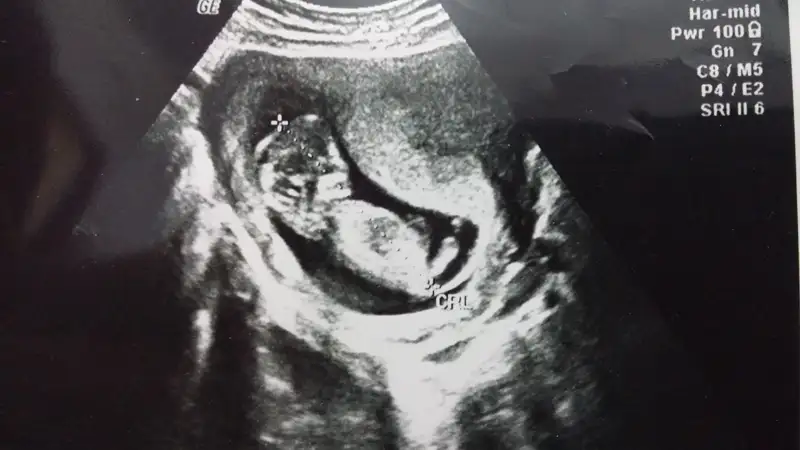

Diğer ultrason görüntülerini atıyorum, lütfen bide bunlara bakarmısın?

Eki Görüntüle 1277161 Eki Görüntüle 1277162

Canim bebisimin fotosunu attim bakarmisin dr soylemiyo erken diyo galiba goruyo ama simdi soylemek olmaz diyo rica etsem siz ne goruyorsunuz ben anlamadim su nub olayinisayfa yöneticisi yurt dışından o yüzden ulaşılamıyo pek yine de bi sorayım

Canim yukari dogru bakan biaey var ama tam olarak nub mu gobek bagimi cozemedim bacaklariyla kapamis gibj:)Eki Görüntüle 1279243 Eki Görüntüle 1279245 Arkadaslar burda 12+5 gunluguz cok merak ediyorum tahmin de bulunabilirmisiz